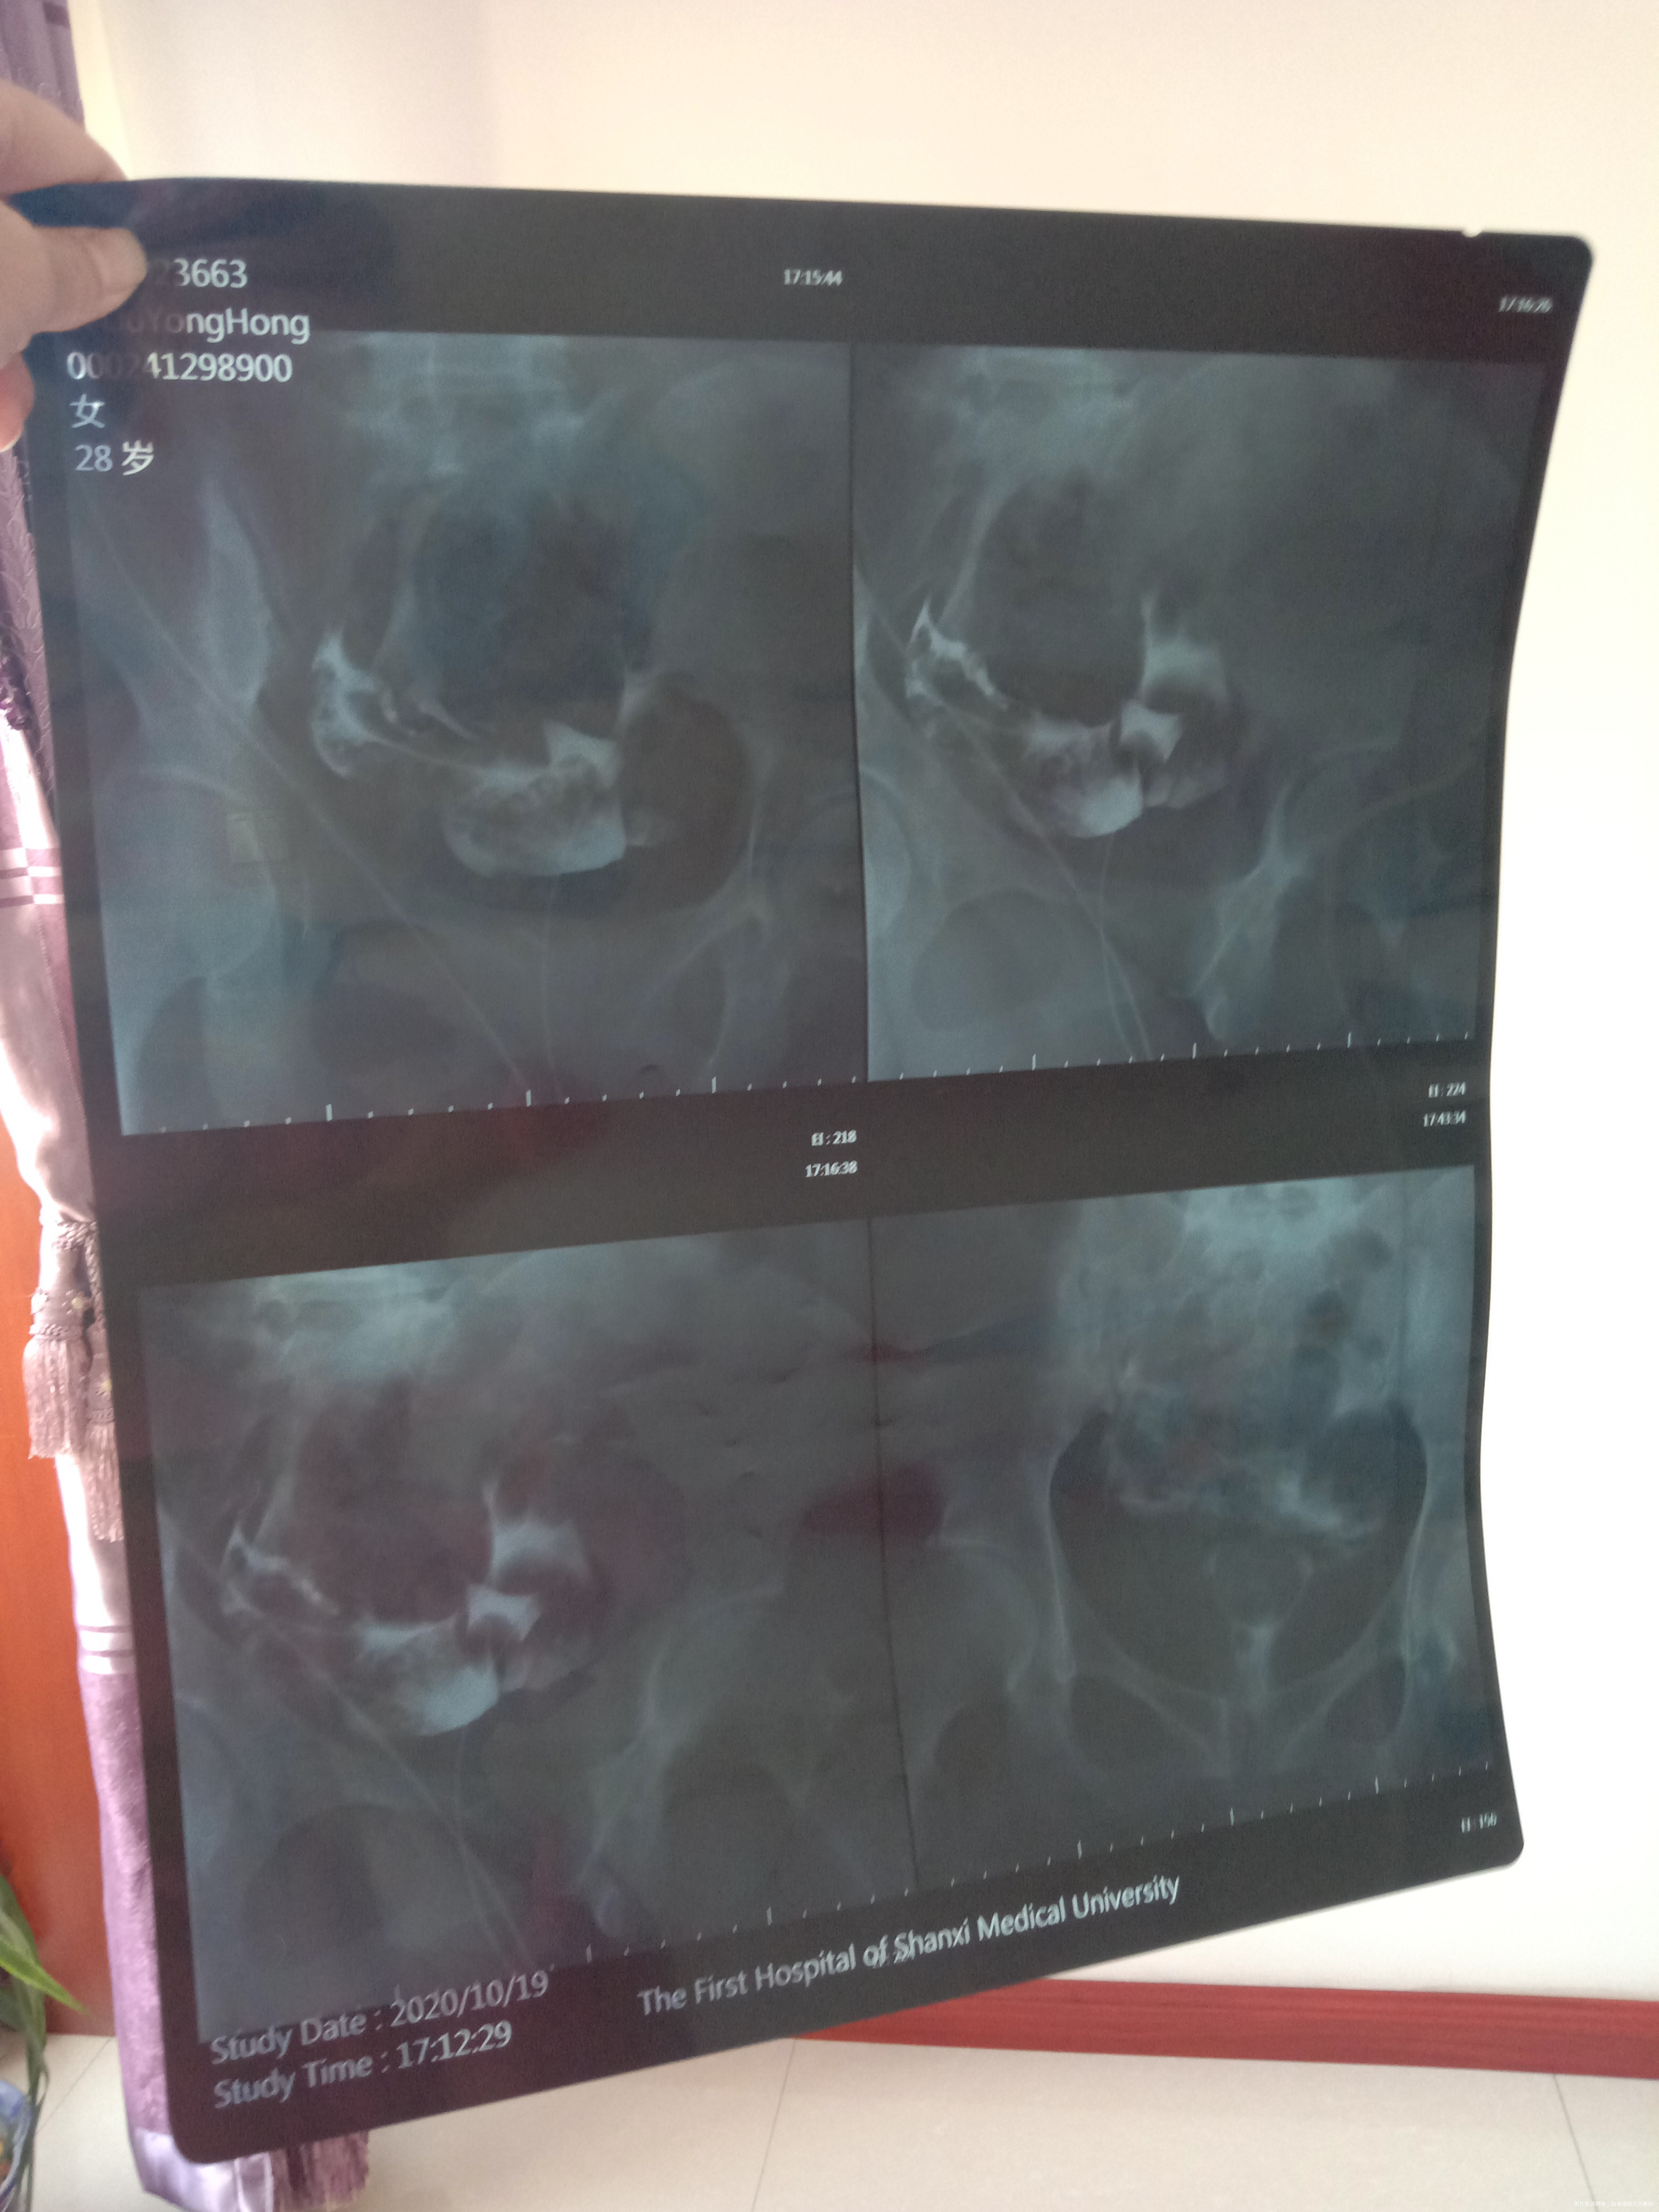

结婚5年,一直检查原因不明,就是怀孕怀不上,不知道这是怎么回事了,下一步需要做啥检查了,还是直接试管了